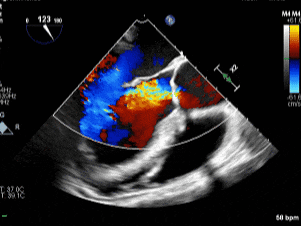

术前主动脉瓣反流

(食道中段主动脉瓣长轴切面)

6.主动脉瓣环径约3.17cm,窦部内径约4.40cm,升主动脉内径约4.38cm。三维超声示主动脉瓣稍增厚,回声稍增强,呈斜裂二叶活动,左右冠瓣可见一个融合回声,开放自如,大量反流。

1.主动脉瓣二叶式畸形(Type 1型):主动脉瓣重度关闭不全,主动脉根部及升主动脉增宽;2.左心增大,左室整体收缩功能正常范围;3.三尖瓣少量反流。